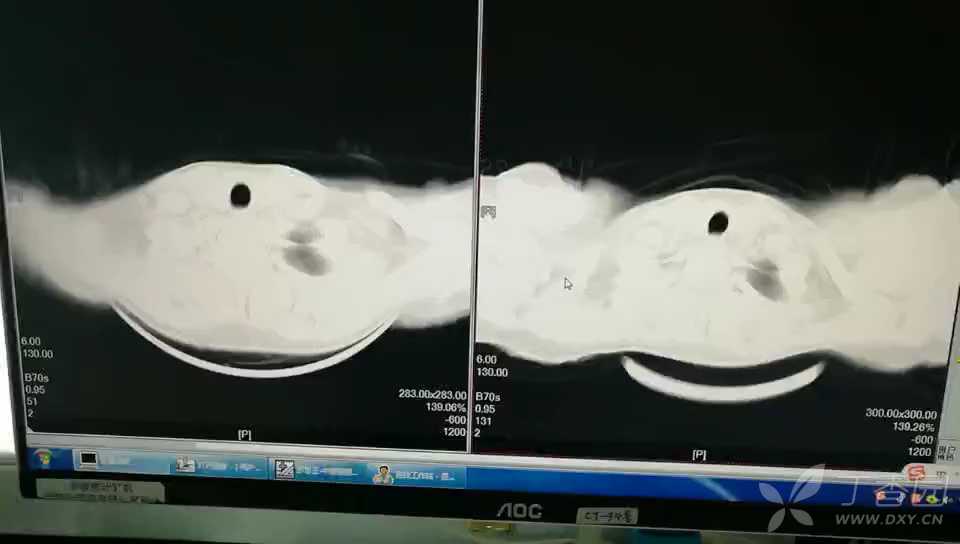

下面是住院期间检查结果,由前到后,有CT 对比视频。

转转感染科后给盐酸莫西沙星抗感染,余下按照新冠治疗,并少量激素使用,25号复查CT 病灶无变化,期间发热最高39.4℃,2月26加用美罗培南后患者热峰下降,期间最高体温38.0℃,2月29号CT 病灶有所吸收,3月2后未发热,期间无特殊症状及不适。3月4号CT 病灶继续吸收,由于未满18岁,3月4号停止莫西,独立使用美罗,3月8号复查CT 病灶整宽,密度曾高,停用美罗培南,更换阿奇霉素+头孢哌酮舒巴坦钠抗感染治疗,3月12胸部CT 对比病灶又增多。期间患者只有单声咳嗽,余下无特殊。住院18天我院多次会诊,治疗效果不明显,2020-3-13转昆明了,3月22电话追问,现在也没出结果。